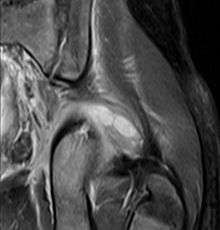

Transverse T2 magnetic resonance imaging section through the hip region showing abscess collection in a patient with pyomyositis.